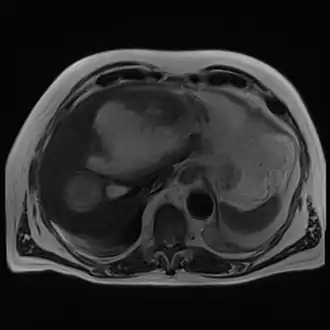

Magnetic resonance cholangiopancreatography (MRC) image showing a voluminous and heterogeneous collection in the left liver lobe (amoebic abscess)